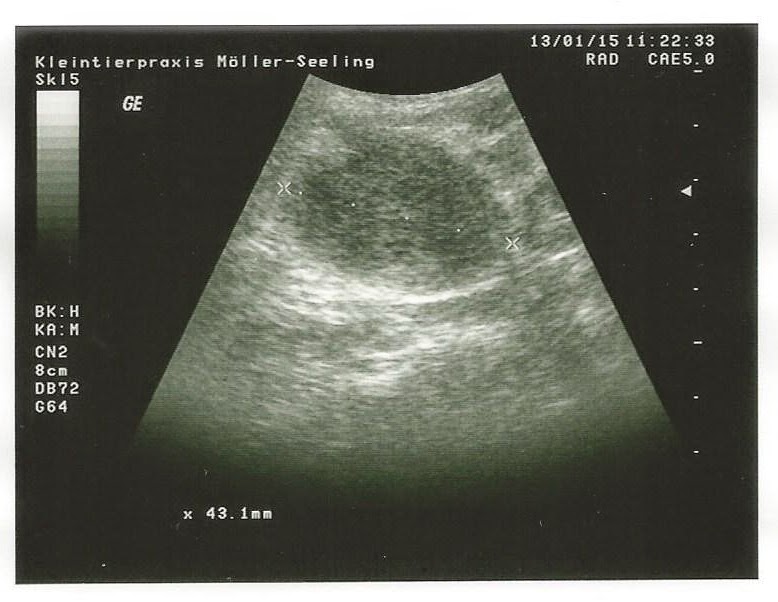

Kleintierpraxis Itzehoe Interessante Fälle